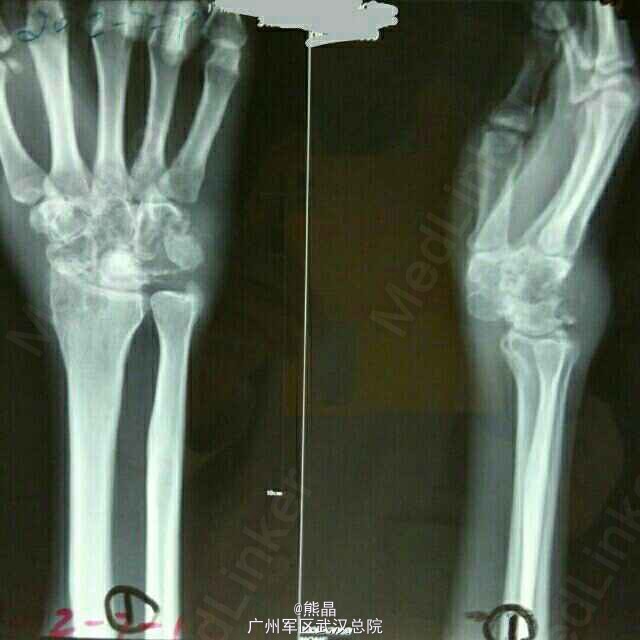

腕关节结核三例

熊医师   中国人民解放军中部战区总医院

腕关节结核在上肢关节中居第三位。病灶多开始于骨骼,或同时累及滑膜,单纯为滑膜型者少见。 病理上干酪型多于肉芽型。多见于青少年,10岁以下较少发病,病灶较易侵犯腱鞘而影响手的功能。脓肿易穿破皮外形成窦道。 X线表现,早期单纯滑膜结核,可见骨质疏松和软组织肿胀。尺桡骨下端结核可有死骨中心型和溶骨性破坏的边缘型。晚期可见多个腕骨尺,桡下端和掌骨关节面广泛破坏。腕关节出现畸形。